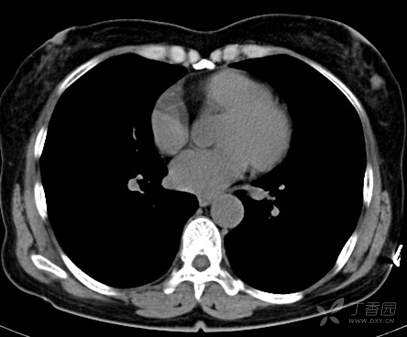

CT